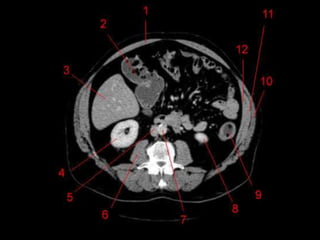

Vasos Hepáticos

• Veia porta

– Formada pela união da Veia Esplênica e Mesentérica

Superior

• Artéria Hepática

– Segmento da Tronco Celíaco

– Dividida em Comum e Própria pelo surgimento da artéria

gastroduodenal.

• Na maioria das pessoas, a artéria é anterior a veia

(91%). Na maioria das pessoas, a artéria hepática

direita passa atrás do ducto hepático comum. (64%)

Vasos Hepáticos • Veiaporta – Formada pela união da Veia Esplênica e Mesentérica Superior • Artéria Hepática – Segmento da Tronco Celíaco – Dividida em Comum e Própria pelo surgimento da artéria gastroduodenal. • Na maioria das pessoas, a artéria é anterior a veia (91%). Na maioria das pessoas, a artéria hepática direita passa atrás do ducto hepático comum. (64%)